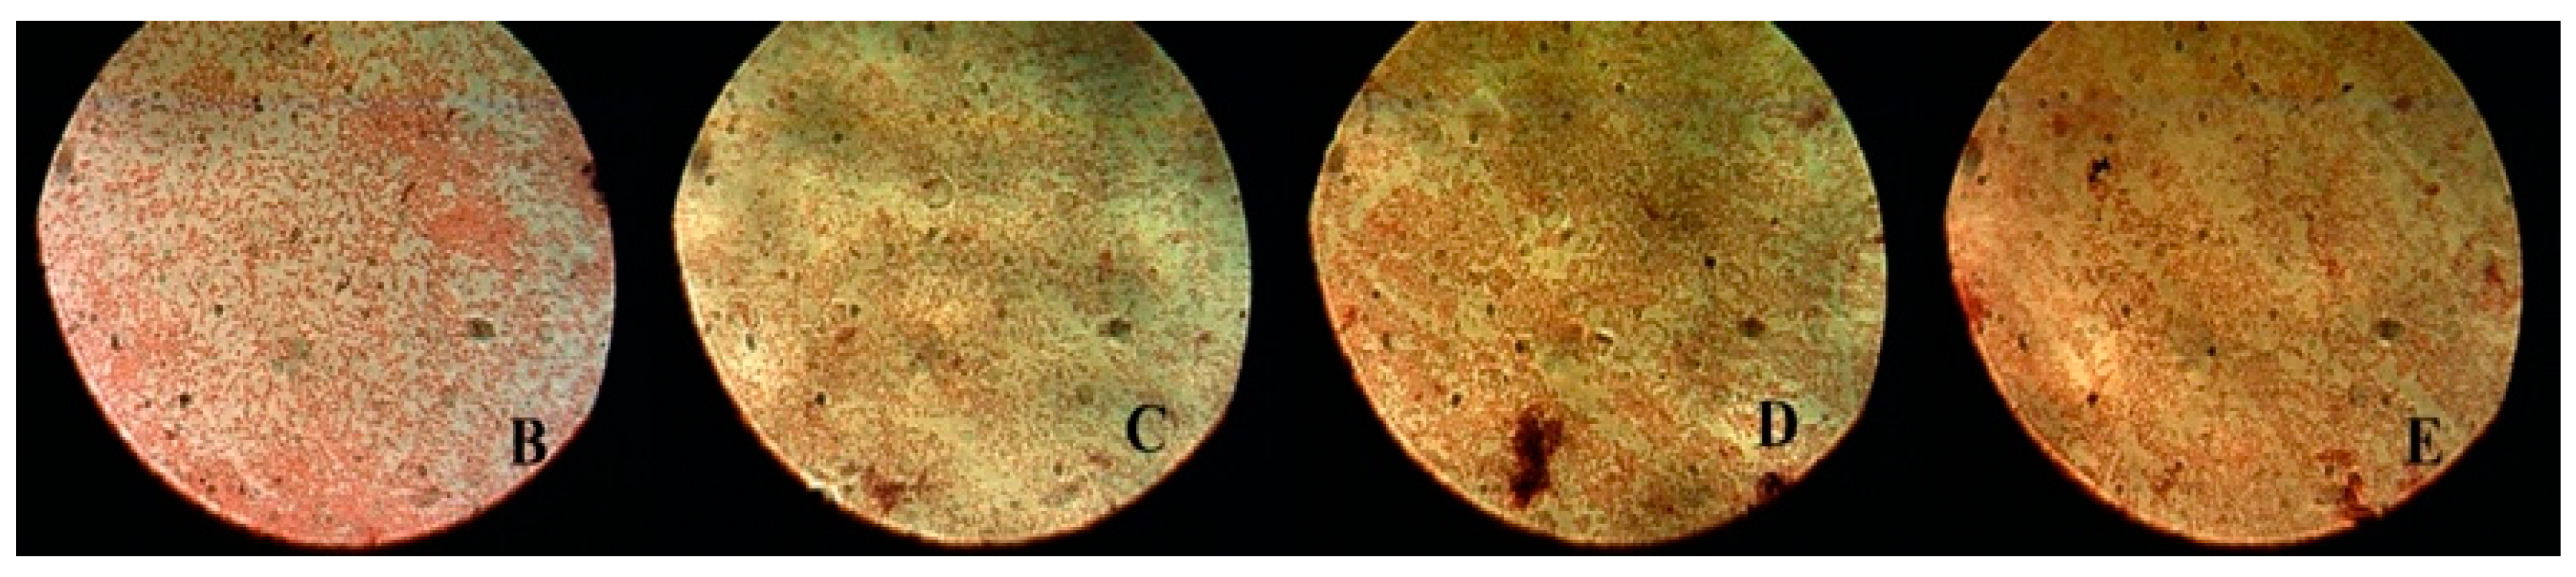

After counting the bacterial colonies, the samples were examined using an optical microscope (OPTIKA, B-600Tiph, Italy, 100×/1.25× oil PH, PLAN) in order to characterize the bacterial colonies. The bacterial colonies were evaluated in two stages: the first after bacterial inoculation for groups B, C, D, and E (Figure 4) and the second after applying all the interventions: MB, MB + PDT, CHL–PC, CHL–PC + PDT, and 2% CHX (Figure 5).

Figure 4. Characterization of bacterial colonies after sample inoculation for groups B, C, D, and E using an optical microscope (OPTIKA, B-600Tiph, Italy, 100×/1.25× oil PH, PLAN).